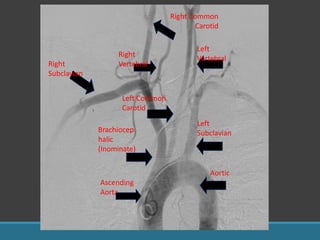

Brachiocep

halic

(Inominate)

Left Common

Carotid

Left

Subclavian

Right

Vertebral

Right Common

Ascending

Aorta

Aortic

Arch